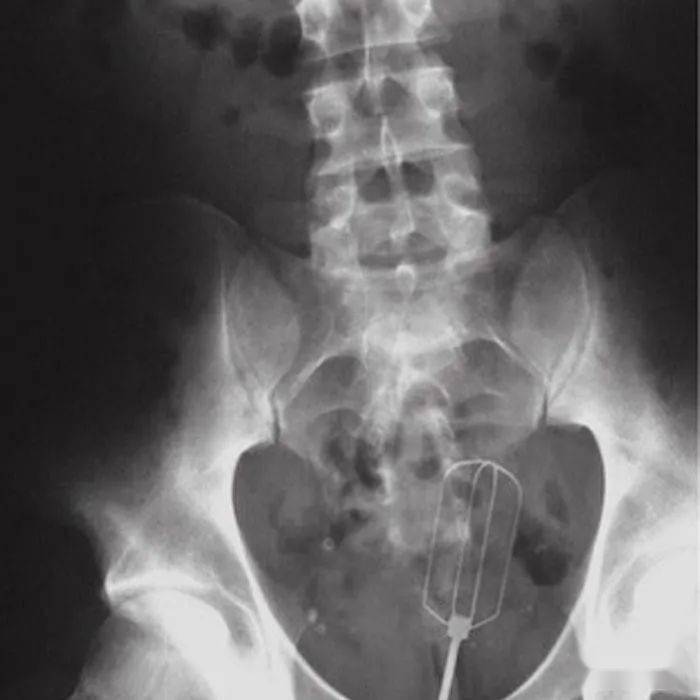

▷打蛋器或许 , 跟上面那个塞鸡蛋的可以认识一下?